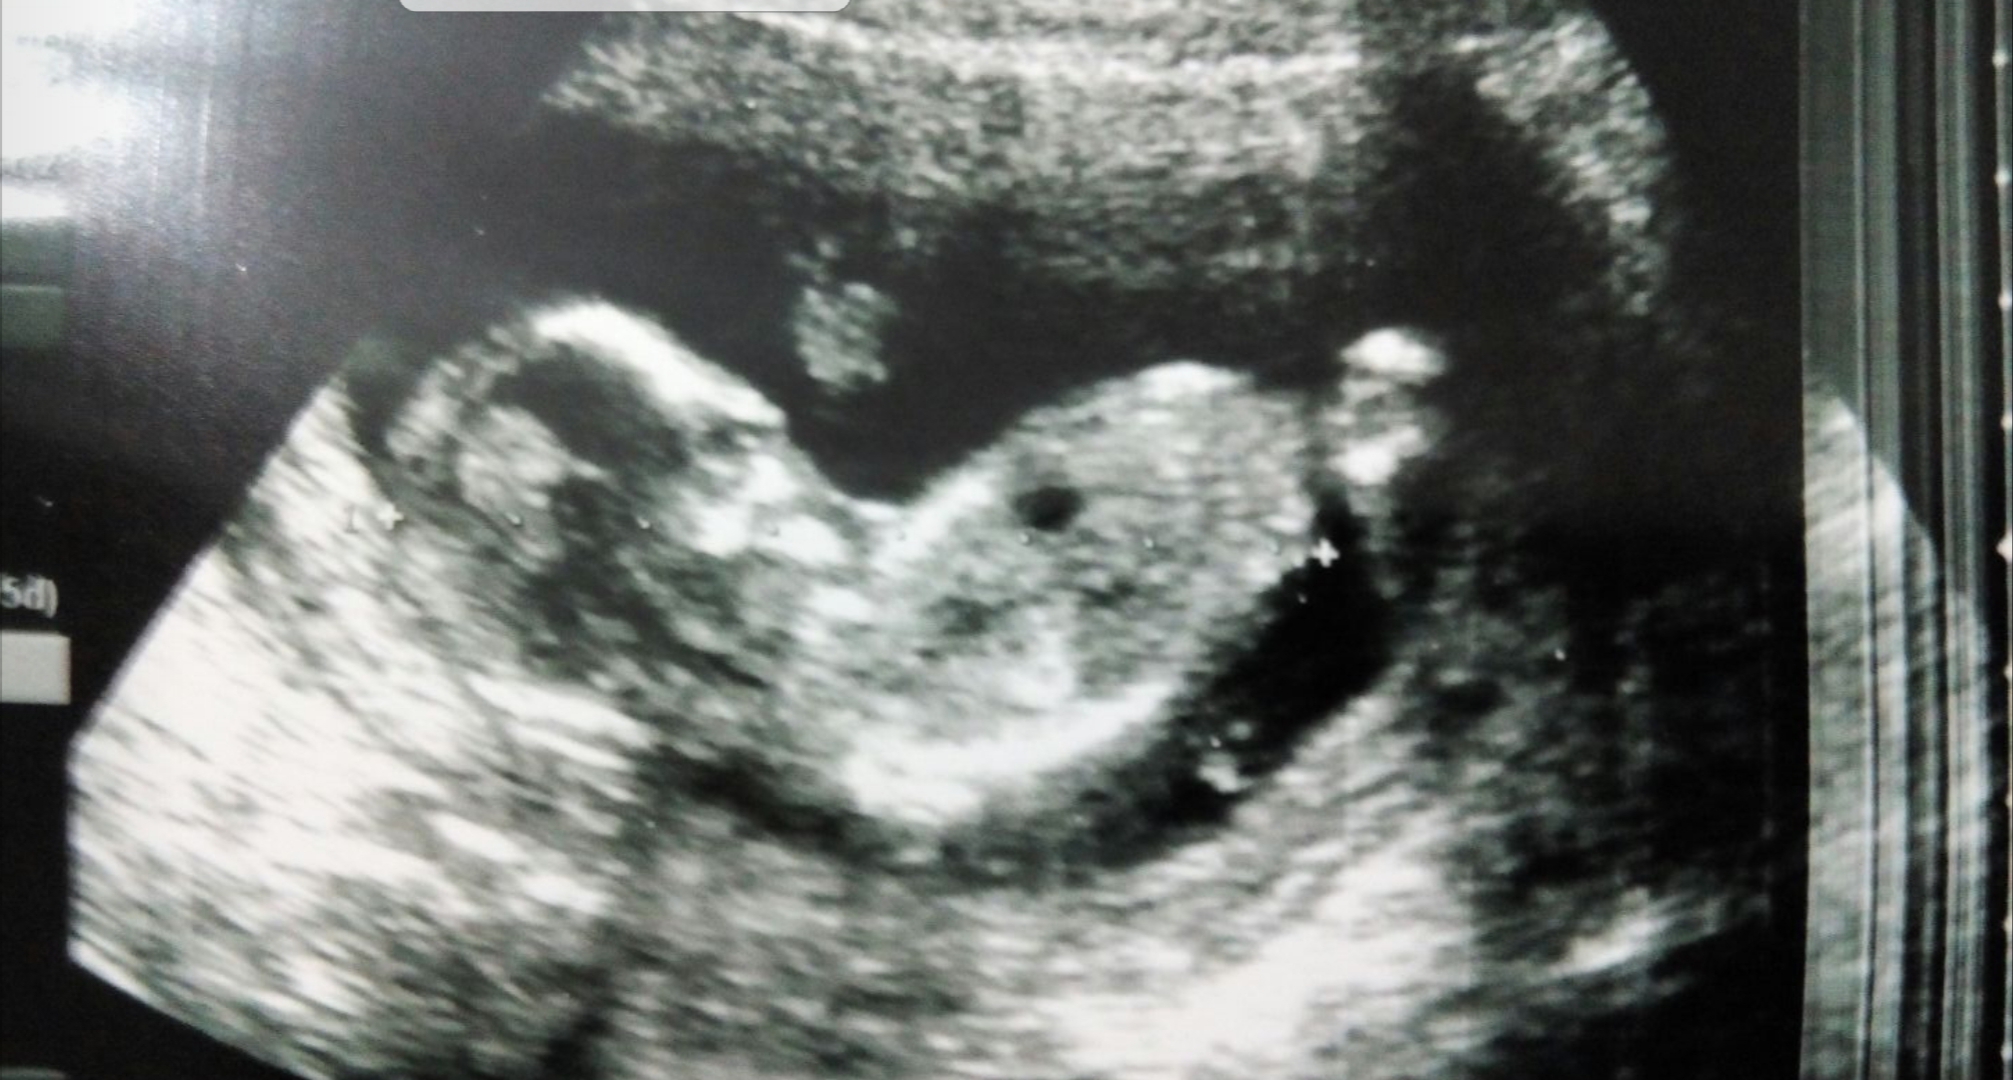

Resimde gördüğünüz gibi üst taraftaki çıkıntı paralel ise bebek kız, 30° lik açıyla yukarı bakıyorsa bebek erkektir.

Gebeliğin 9. haftası fetusun bacaklarının arasın da küçük bir çıkıntı görülür. Gebeliğin 12. ve 14 haftası bu topak çıkıntı nın açısı değerlendirilerek , cinsiyet tahmini yapılır. Çıkıntı kızlar da 30 derecenin altın da ve düzdür erkekler de ise 30 derecelik açıdan büyüktür.

Görünürlük , omurga ile ilgili genital tüberkül açısı , Gölgeler ve erkek belirteçler ve topak çevreleyen ucu , Gebelik yaşına göre uzunluğu da dahil olmak üzere, şekil.. Nub teorisi ile cinsiyet belirleme de tarama omurga görüntüleme ve buna özü ilişkisini sağlamak için, profil görünümünde olmalıdır.

Merhaba, ultrason görüntünüzün kalitesi iyi değil. Nub çıkıntısı belirsiz .Emin olmamakla birlikte bebeğinizin cinsiyetinin kız olduğu kanısındayım. Hatırlatma fayda var bebeğinizin cinsiyetini net olarak 17-19-20. haftalarda öğrenebilirsiniz.